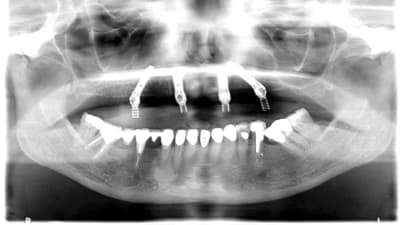

Continuing Education Implants The “All-on-4” Concept for Implant Rehabilitation of an Edentulous Jaw By Christopher CK Ho, BDS, Sascha A. Jovanovic, DDS April 01, 2014